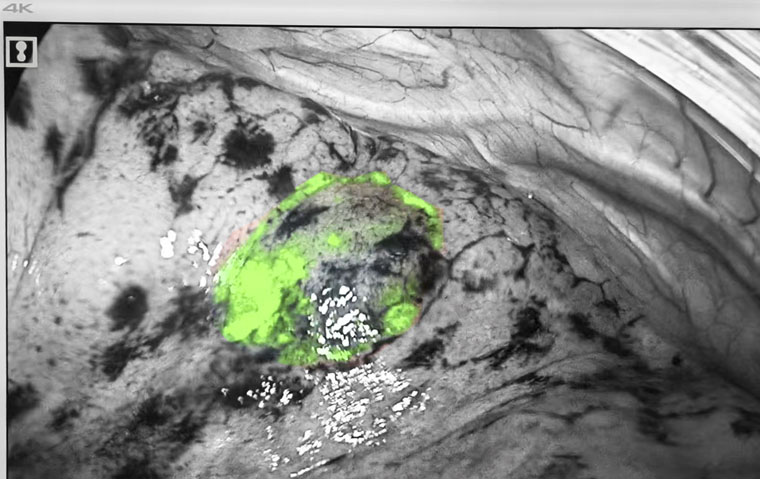

熒光顯影標記

手術在麻醉三科賈麗主任團隊全程保障及東院手術室護理團隊的協助下進行。黃超主治醫師操作電磁導航支氣管鏡,胸科內鏡室張金澤技師長、邊媛媛主管護師全力配合。患者全麻后,醫療團隊經氣管插管進鏡,在電磁導航的實時指引下分別到達兩處病灶位置,并將熒光顯影劑通過內鏡鞘管分別滴注至兩處病灶定位標記,整體操作時間僅10余分鐘。定位后,胸腔鏡手術隨即進行。熒光模式下,在肺表面即可看到定位的熒光顯影標記,術者對病灶進行精準切除。術中快速冰凍病理顯示,右肺上葉前段楔形考慮微浸潤性腺癌,肺上葉后段楔形肺組織內可見纖維化結節,周邊局灶肺泡上皮非典型增生,最終石蠟病理回報吻合口切緣陰性,表示邊緣未發現腫瘤細胞,手術已完整切除病變。